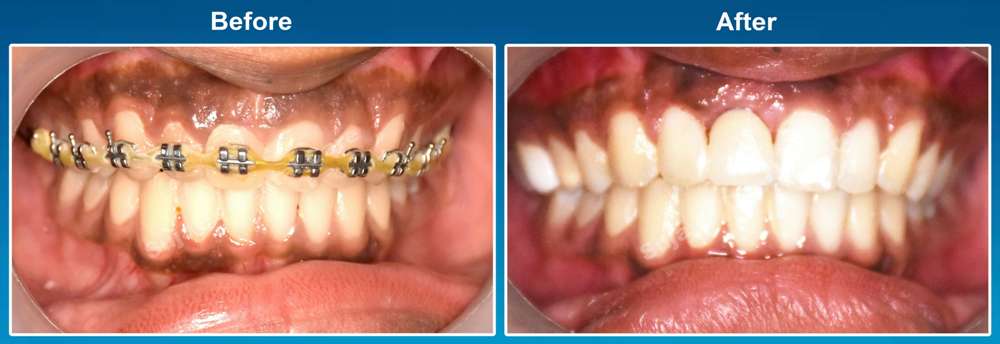

Before & After